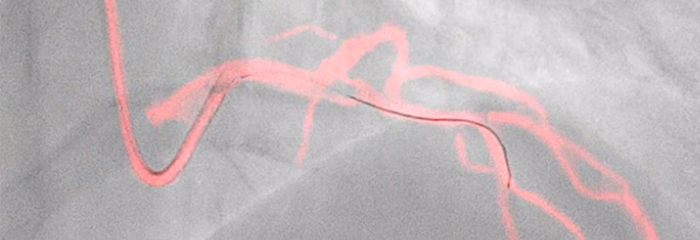

OmniWire

Pressure guide wire

OmniWire combines a unique solid core workhorse design with iFR proven outcomes and iFR Co-registration compatibility, making it easy to use physiology throughout complex cases.¹,²,³ New Nitinol distal core increases durability and shape recovery. Unique solid core improves torque and pushability. Integrated conductive bands for greater signal reliability.